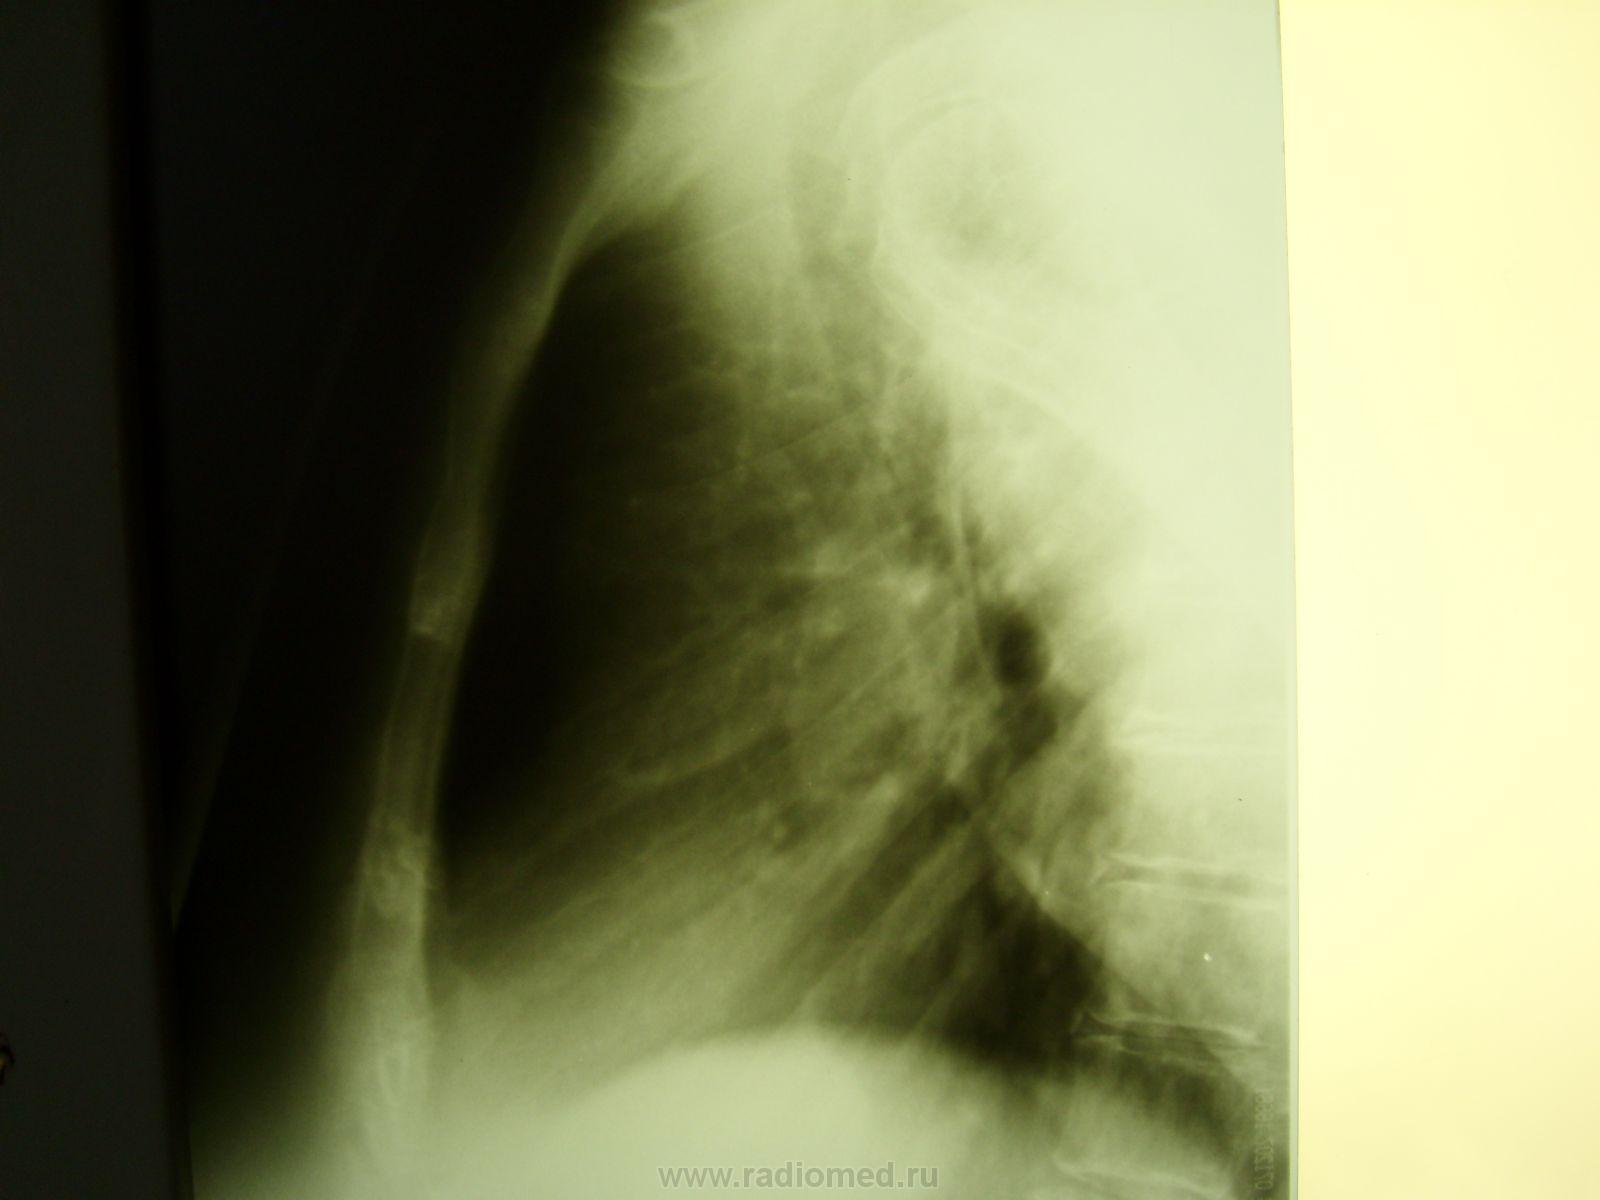

Пол пациента: Женский пол Тип патологии: Травма Область исследования: Грудная клетка и верхние дыхательные пути Методы исследования: Rg Женщина поступила в приёмное отделение после "конфликта" с сожителем https://radiomed.ru/sites/default/files/styles/case_slider_image/public/user/712/sl273142.jpg?itok=k9kzdr31 ID:22279 Втр, 28/09/2010 - 06:16 #1 mila Не на сайте Был на сайте: 5 лет 2 месяцев назад Зарегистрирован: 26.02.2010 - 02:56 Публикации: 277 Не понятно что делали? Если обзорный, почему левое легочное поле срезано? Почему на боковом снимке рука? Втр, 28/09/2010 - 20:39 #2 Глазков Игорь А... Не на сайте Был на сайте: 9 месяцев 1 неделя назад Зарегистрирован: 19.12.2008 - 20:41 Публикации: 1597 проводили для исключения перелома рёбер и пневмогемоторакса Прийди к Себе Ср, 29/09/2010 - 02:47 #3 mila Не на сайте Был на сайте: 5 лет 2 месяцев назад Зарегистрирован: 26.02.2010 - 02:56 Публикации: 277 Певмоторакса нет, руку наверное поднять не может, может перелом плечевого отростка лопатки? Чт, 30/09/2010 - 17:34 #4 Helios Не на сайте Был на сайте: 7 месяцев 2 недели назад Зарегистрирован: 06.08.2010 - 15:16 Публикации: 4417 Ключично-акромиальный сустав еще посмотрите.Каков механизм травмы?Было бы понятнее, что еще можно визуализировать. Сб, 14/07/2012 - 14:10 #5 Махамбетчин Мур... Не на сайте Был на сайте: 3 недели 6 дней назад Зарегистрирован: 14.07.2012 - 10:44 Публикации: 1205 Если это снимок лежа, то больше похоже на гемоторакс слева с незначительным смещением средостения вправо.

Не понятно что делали? Если обзорный, почему левое легочное поле срезано? Почему на боковом снимке рука?

проводили для исключения перелома рёбер и пневмогемоторакса

Певмоторакса нет, руку наверное поднять не может, может перелом плечевого отростка лопатки?